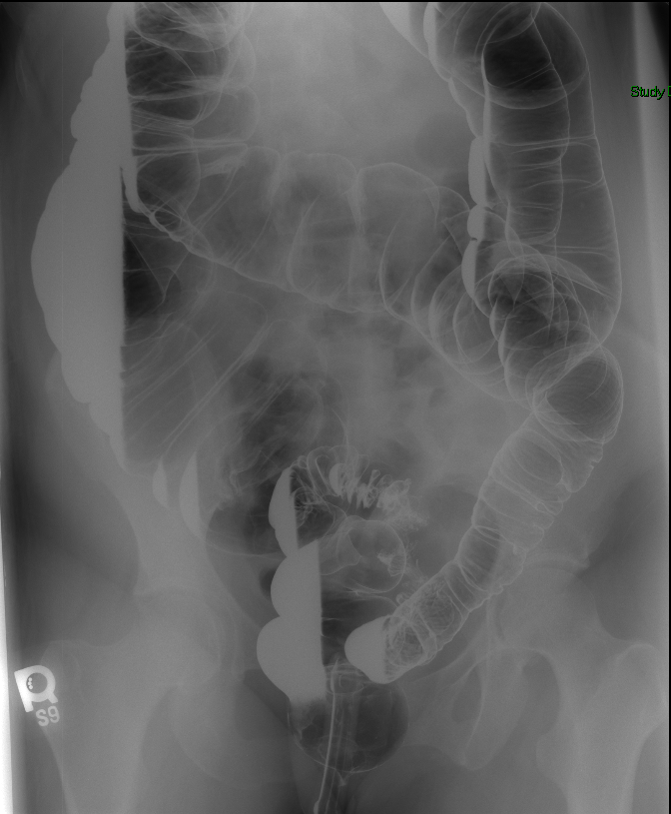

- Once the barium has reached the small bowel, you will go into the room and obtain spot images of the contrast material filled small bowel.

- Obtain images of the terminal ileum and the ileocecal valve filled with contrast material

(key image 6)

(key image 7)

(key image 8)

(key image 9)

(key image 10).

- Obtain spot images of the remainder of the small bowel

(key image 11)

(key image 12)

(key image 13)

(key image 14).

- Obtain images of all four quadrants. Use the compression paddle to separate loops of small bowel from each other.